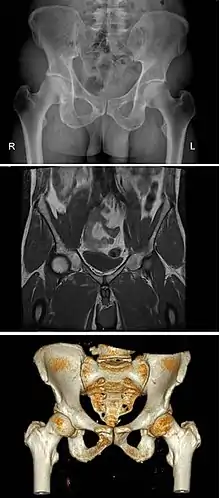

A história da anatomia caracteriza-se pela progressiva compreensão das funções dos órgãos e estruturas do corpo humano. Nos últimos séculos, os métodos de observação evoluíram de forma significativa, desde a dissecação de carcaças e cadáveres até às técnicas modernas de imagiologia médica, entre as quais radiografia, ecografia e ressonância magnética.

A invenção do microscópio eletrónico em 1931 permitiu aumentar drasticamente o poder de resolução, o que veio permitir observar a ultraestrutura das células e das organelas e outras estruturas no seu interior. Na década de 1950, a introdução da cristalografia de raios X para o estudo das estruturas proteicas, ácidos nucleicos e outras moléculas biológicas deu origem ao novo campo da anatomia molecular.[104] A radiação eletromagnética de onda curta, como os raios X, é capaz de atravessar o corpo e é por isso usada em radiografia clínica para observar estruturas anatómicas com diferentes graus de opacidade. Hoje em dias, as técnicas mais modernas como a imagem por ressonância magnética, tomografia computorizada, fluoroscopia ou ecografia permitem aos investigadores e profissionais de saúde examinar as estruturas anatómicas, vivas ou mortas, com detalhe sem precedentes.[105]